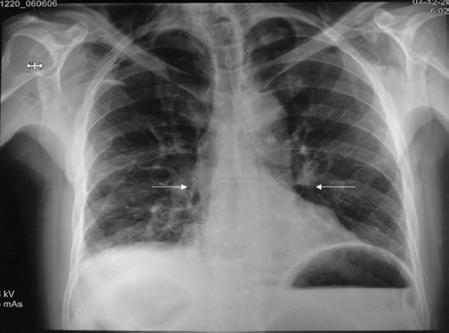

En la exploración física el paciente se encuentra despierto, escala de Glasgow 15 puntos, facies álgica, polipneico, con enfisema subcutáneo en la región supraclavicular y el tórax superior bilateral con crepitación, sin equimosis, con requerimiento de oxígeno suplementario por puntas nasales a 5 l/min, con disminución del murmullo vesicular en la región basal del hemitórax derecho y dolor abdominal a la palpación superficial y profunda en la región epigástrica, así como intolerancia al decúbito supino. El resto de la exploración no mostraba alteraciones, con los siguientes signos vitales: presión arterial 130/80 mmHg, frecuencia cardiaca 100 latidos por minuto, frecuencia respiratoria 20 respiraciones por minuto, temperatura 36.6 °C, saturación de oxígeno 96% y fracción inspirada de oxígeno 30%. Los parámetros de laboratorio fueron: hemoglobina 15.7 g/dl, hematocrito 45.9%, leucocitos 12.3 × 103/ml, glucosa 128 mg/dl, procalcitonina 34 ng/ml y troponina I < 0,04 ng/ml. El electrocardiograma mostró ritmo sinusal, frecuencia cardiaca 97 latidos por minuto, AQRS 0°, QRS 0.12 s y sin alteraciones del segmento ST. Se decidió realizar una radiografía de tórax, en la que se observó un enfisema subcutáneo en la región supraclavicular y ensanchamiento del mediastino (Fig. 1), y una tomografía computarizada de tórax con medio de contraste oral hidrosoluble, que confirmó el enfisema subcutáneo con extensión hasta la región escapular bilateral. También se observó neumomediastino bilateral, neumopericardio y fuga del medio de contraste hidrosoluble a nivel del tercio inferior del esófago hacia el mediastino medio, la cavidad pleural y el pericardio (Figs. 2 a 4). Se inició antibioticoterapia intravenosa (betalactámico y clindamicina).

Figura 1 Radiografía de tórax posteroanterior en la que se observa un enfisema subcutáneo en el cuello y la región supraclavicular bilateral, así como ensanchamiento del mediastino y dilatación ventricular (flechas).